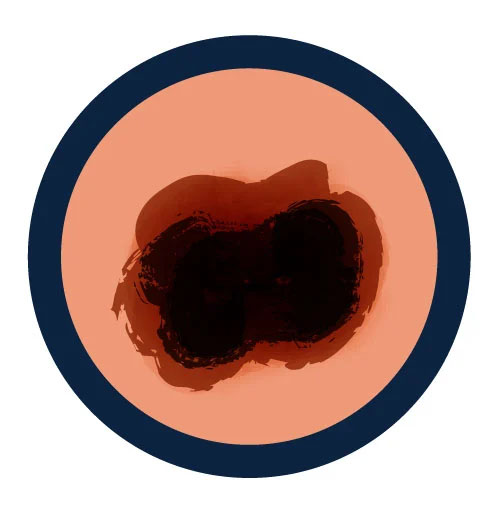

A is for Asymmetry

One half of a mole or spot does not match the other.

B is for Border

The edges of the spot are irregular, scalloped or poorly defined.

C is for Color

The color of the spot is not the same all over and may include different shades of brown or black, sometimes with patches of pink, red, white or blue.